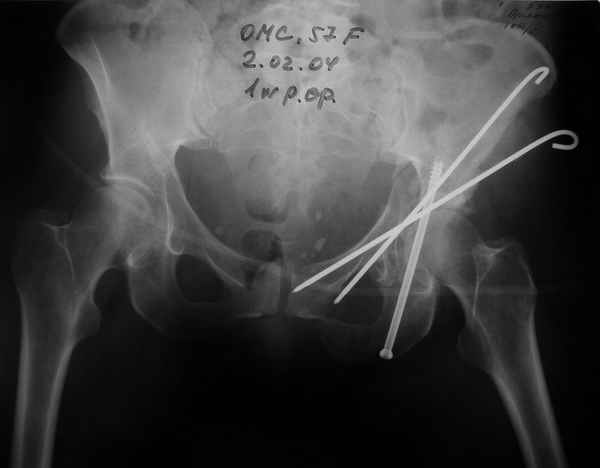

Не дождавшись советов, в понедельник прооперировал больного, заняло времени..., но все сделал в один этап: сначала фиксировал ипсилатеральный перелом бедра и шейки реконструктивным гвоздем Smith&Nephews, потом из расширенного илеофеморального доступа фиксировал перелом крыла подвздошной кости тягловым винтом, нейтрализующей пластиной заднюю колонну, и тягловыми винтами 3,5 мм переднюю колонну.

Несмотря на расширенный доступ, особой кровопотери не было, перелил только одну дозу эр.массы и на утро Нв- 10.5 и как ни странно больной не жалуется на сильные боли и стопа не *висит*, хотя при интраоперационной ревизии седалищного нерва обширная гематома в периневральной оболочке.

К сожалению, набора для ретроградного или антеградного реконструктивного штифтования в операционной нет, поэтому доставка заняла н-ное время. Вопрос, который возник у меня- по поводу оптимальной тактики хирургии: вся фиксация в один этап из расширенного доступа или последовательно сначала бедро и позже реконструкция впадины, комбинированный доступ к впадине отдельно к передней и задней колоннам или из расширенного илеофеморального одного доступа. Все-таки решил остановиться на одноэтапном подходе и спустя 5 дней (как раз и наборы привезли) из расширенного илеофеморального доступа сначала фиксировал реконструктивным штифтом Smith&Nephews бедро и

шейку (благо перелом шейки 2 типа -относительно стабильный) затем фрагмент крыла подвздошной кости Lag screw, далее пластина на заднюю колонну и винты в переднюю колонну.(с размерами и направлением винтов ошибка вышла:-((, но интраоперационно у меня была полная уверенность , что винты *ушли* в лонную кость).

Еще раз спасибо за комментарии и готовность помочь с имплантами. Постоп картинки в приложении,